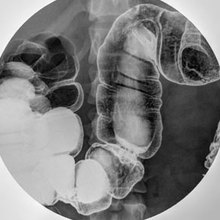

结肠气钡双重造影

结肠气钡双重造影,又称结肠双对比造影,是检查直肠与结肠的形态,有无梗阻或狭窄的一种方法。

三、患者仰卧左后斜位,在透视指导下注人钡剂,至结肠脾曲停止。令患者向左旋转成俯卧位,使钡剂自行流人横结肠。使降结肠位于高处。然后注入空气,使空气由下位之直肠、乙状结肠向上升至降结肠、将空气前方之钡剂推送到升结肠,盲肠。 医学百科网 | YxBaike.Com

四、拔除肛管,令患者绕体纵轴翻滚数次,使钡剂均匀涂布在结肠粘膜面上。 医学百科网 | YxBaike.Com

五、利用体位使空气上升,钡剂下降,分段摄取结肠双重造影片。 医学百科网 | YxBaike.Com